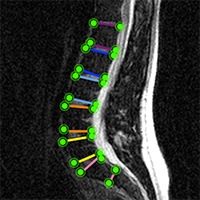

Imaging

Lower Back Pain